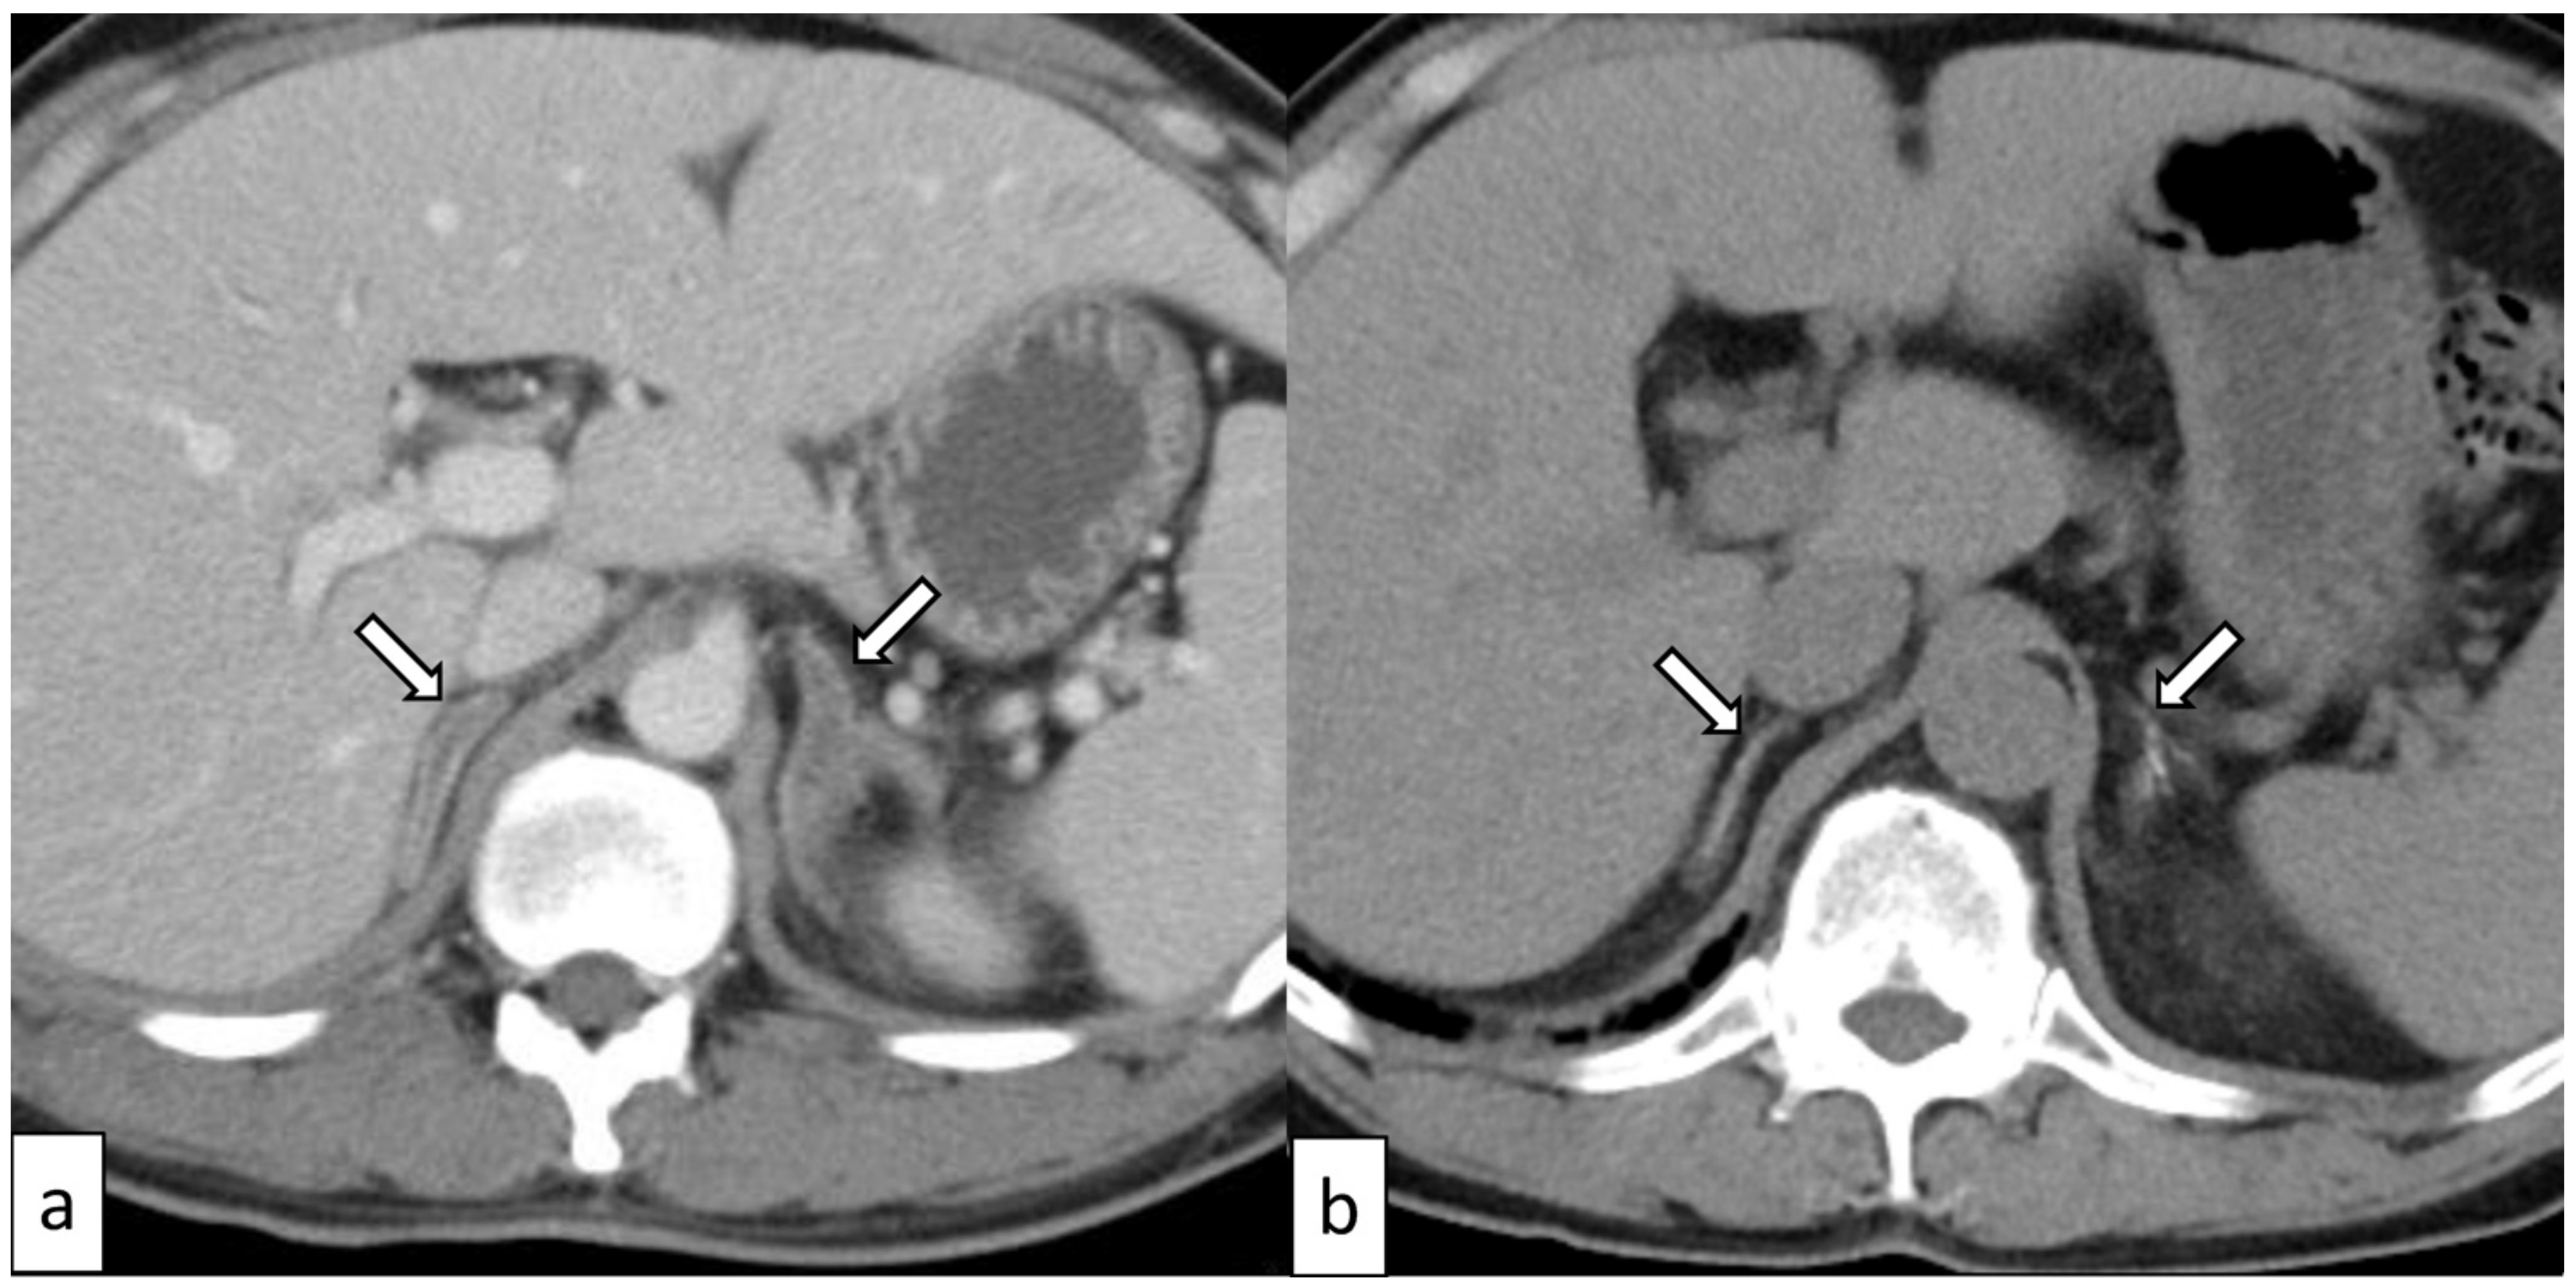

| Our case | 38 (Figure 2) | Male | YES | Ischemia/infarction | Bilateral | YES | YES | YES | YES |

3.4. Adrenal Ischemia/Infarction